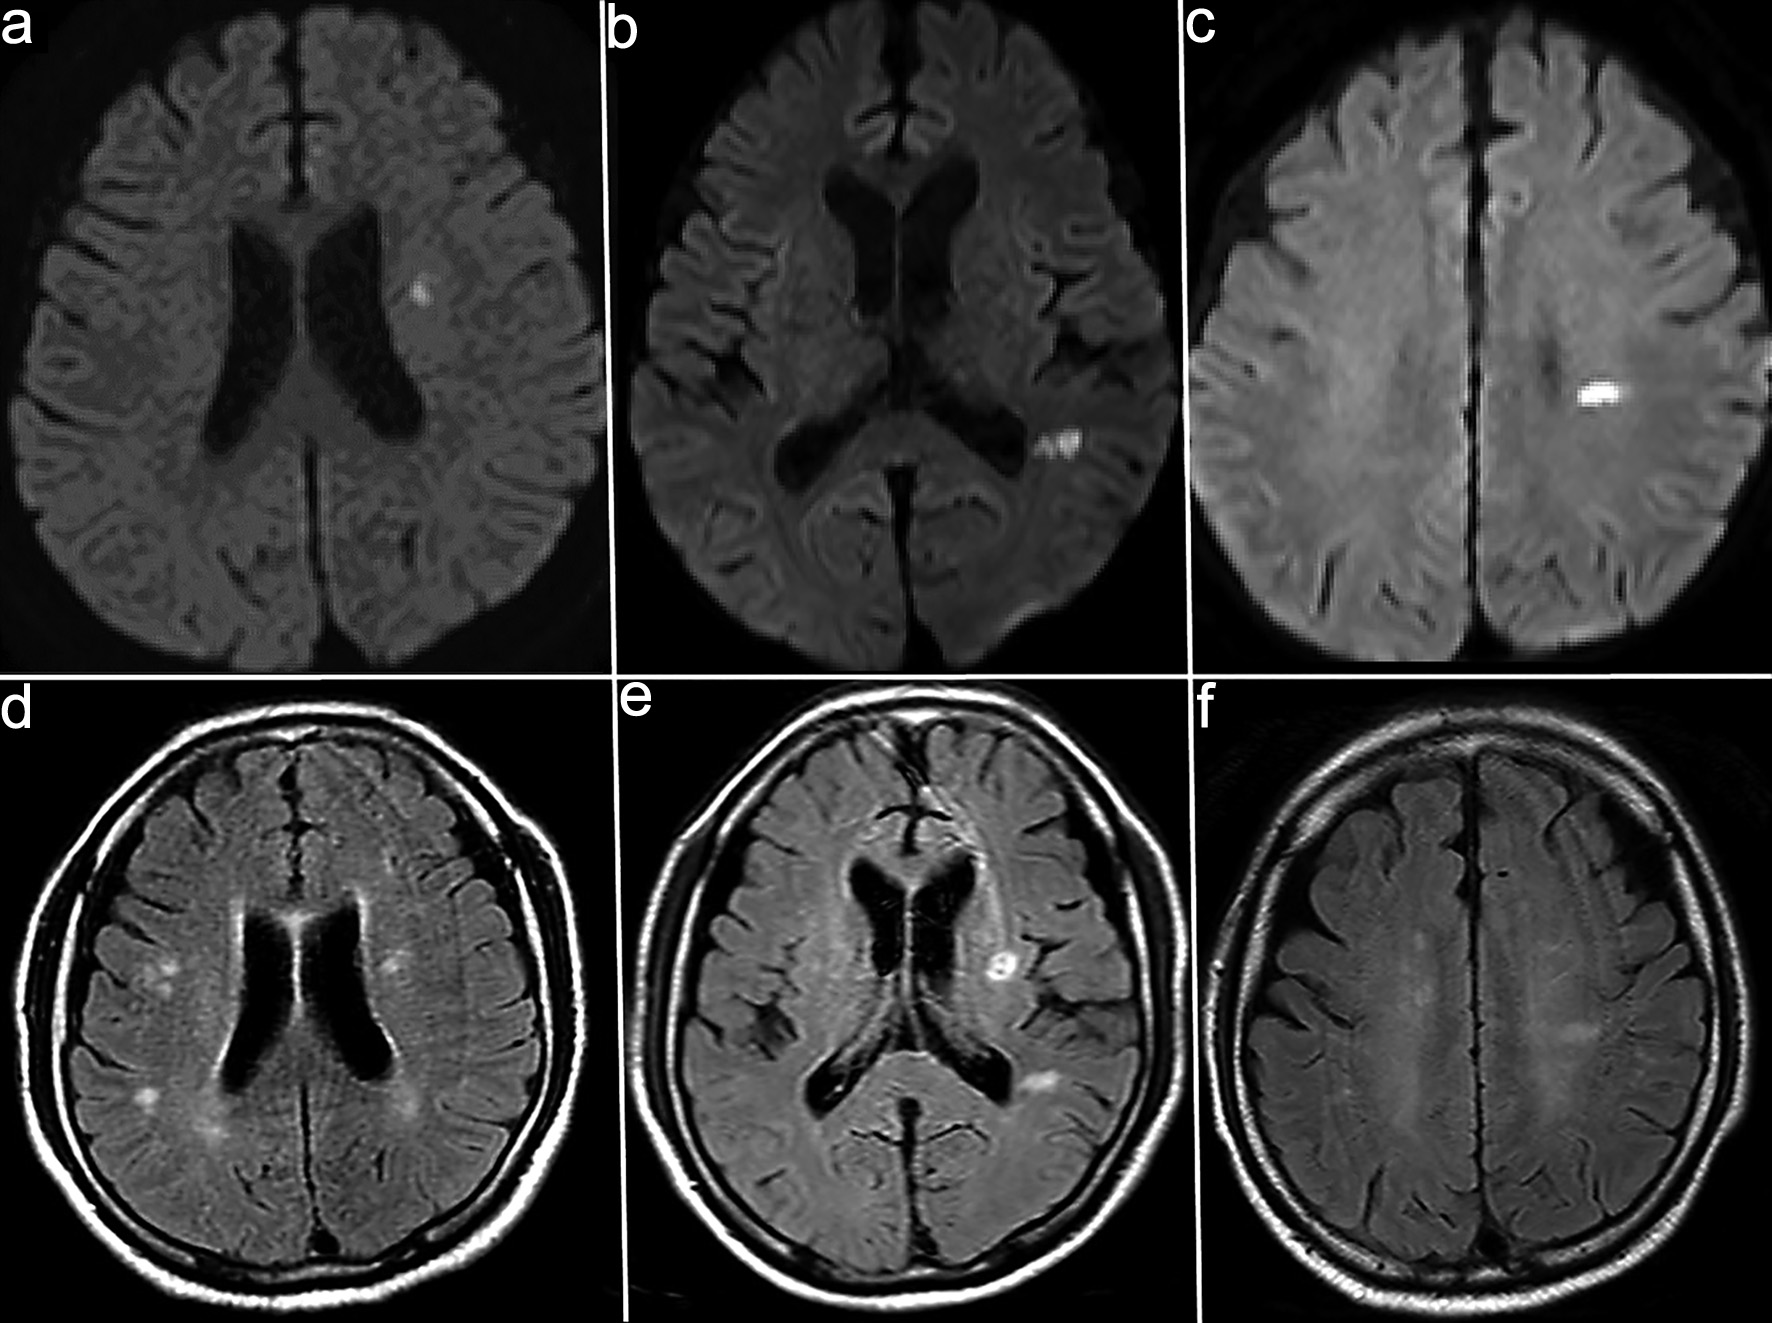

Brain magnetic resonance imaging (MRI) on admission showed a high-intensity lesion in the left thalamus on diffusion-weighted imaging (DWI) with a corresponding low-intensity lesion on the apparent diffusion coefficient (ADC) map, along with multiple spotty white matter lesions on fluid-attenuated inversion recovery (FLAIR) (Fig. 1). Magnetic resonance angiography (MRA) showed no significant stenosis. Cerebrospinal fluid (CSF) analysis revealed pleocytosis (97/mm3), protein elevation (153 mg/dL), and positive oligoclonal bands (six bands). The immunoglobulin G (IgG) index was 0.959. Serum anti-MOG antibodies were positive (titer 1:16, Cell-based assay), whereas anti-aquaporin-4 (AQP4), anti-NMDA, and various paraneoplastic antibodies were negative (Table 1).

Click for large image

Figure 1. Magnetic resonance imaging (MRI) on admission. (a) High-intensity lesion in the left thalamus on diffusion-weighted imaging (DWI). (b) Corresponding low-intensity lesion on the apparent diffusion coefficient (ADC) map. (c) Fluid-attenuated inversion recovery (FLAIR) images demonstrating multiple spotty hyperintense white matter lesions.